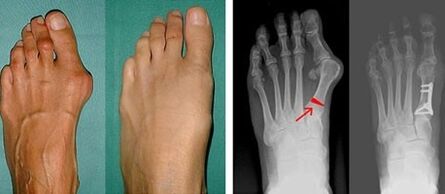

Im ersten Schritt zur Feststellung der Valgusstellung des großen Zehs und des kleinen Fingers führt der Arzt eine visuelle Untersuchung durch. Auf diese Weise wird der Entwicklungsstand der Pathologie bestimmt. Um detaillierte Gelenkveränderungen zu erkennen, sind Röntgenaufnahmen und Plantographie vorgeschrieben.

Wenn die visuelle Untersuchung und das Röntgen keine Ergebnisse liefern, wird der Patient zur Plantographie überwiesen, um mögliche Plattfüße festzustellen. Bei dieser Methode werden Fußabdrücke genommen, aus denen für den Patienten Schuhe oder Einlagen mit orthopädischen Eigenschaften angefertigt werden. Anschließend wird dem Patienten eine Pädometrie verschrieben. Diese Methode nutzt eine Computeranalyse, um den Gewichtsdruck einer Person auf ihre Füße zu bestimmen. Die Ergebnisse der fortgeschrittenen Diagnostik sind die Grundlage für die Wahl einer Behandlungsmethode bei der Krümmung des ersten und zweiten Fingers.